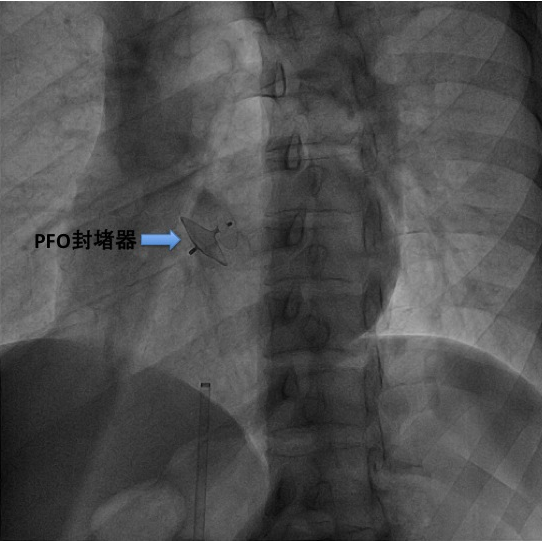

这位年青卒中患者经神经内科系统临床筛查,包括经颅多普勒发泡试验阳性,呈雨帘状;经食道超声提示卵圆孔未闭,直径1.9mm, 右心声学造影阳性,中等量右向左分流,神经内科会诊后认为该患者卒中与卵圆孔未闭有关,为了减少和防止卒中复发,建议进行卵圆孔未闭介入封堵治疗。心血管内科经过充分的术前论证和手术设计,心血管内科介入团队付强副主任医师于2015年5月14日为该患者成功实施了经导管卵圆孔未闭封堵术,术后患者恢复良好。

经导管卵圆孔未闭封堵术的优点:微创,不开刀,只需穿刺股静脉,30分钟完成手术;术后恢复快,2天出院;并发症少,安全性高;不需要体外循环,胸部无术后疤痕;目前使用的封堵器为镍钛记忆合金制成,无抗原性,在体内不会产生排异反应。(心血管内科付强 陈步星)